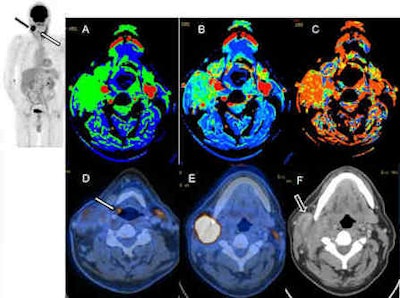

These images are of a 56-year-old man with suspected hypopharyngeal cancer and ipsilateral lymph node metastases. The maximum intensity projection (MIP) image (top left, white arrow) shows the small tumor at the aryepiglottic fold in the right side (D) with focal FDG avidity. Additionally, a large lymph node metastasis with high FDG activity was detected right cervically (black arrow on MIP image and E, F). Perfusion imaging of the large lymph node (A-C) shows elevated blood flow (A), blood volume (B), and also a decreased mean transit time (C). Images courtesy of Dr. Patrick Veit-Haibach.

These images are of a 56-year-old man with suspected hypopharyngeal cancer and ipsilateral lymph node metastases. The maximum intensity projection (MIP) image (top left, white arrow) shows the small tumor at the aryepiglottic fold in the right side (D) with focal FDG avidity. Additionally, a large lymph node metastasis with high FDG activity was detected right cervically (black arrow on MIP image and E, F). Perfusion imaging of the large lymph node (A-C) shows elevated blood flow (A), blood volume (B), and also a decreased mean transit time (C). Images courtesy of Dr. Patrick Veit-Haibach.The primary tumor and inflammatory lesions can be differentiated by CTP values, as well as partially by PET measurement, but further research (especially larger standardized studies) must focus on combined ratios of CTP and PET values to lead to a better understanding of the relation between tumor perfusion and glycolytic rate, according to the authors.